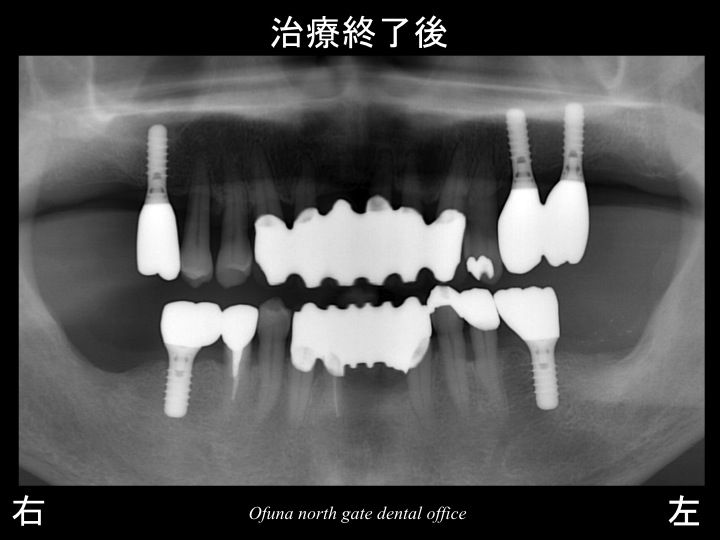

以下は治療終了後です。

今回の治療により以下のことが達成できました。

1.歯周病が治った!

歯肉の腫れも治り、出血もなくなりました。

当然残っている歯の将来性が高まったのです。

2.ブリッジにより、グラグラの歯が治まった!

3.インプラント治療により奥歯で噛めるようになった!

前歯の負担が少なくなり、将来性が高くなった!

今回使用したインプラントは全てストローマンインプラント(ITIインプラント)